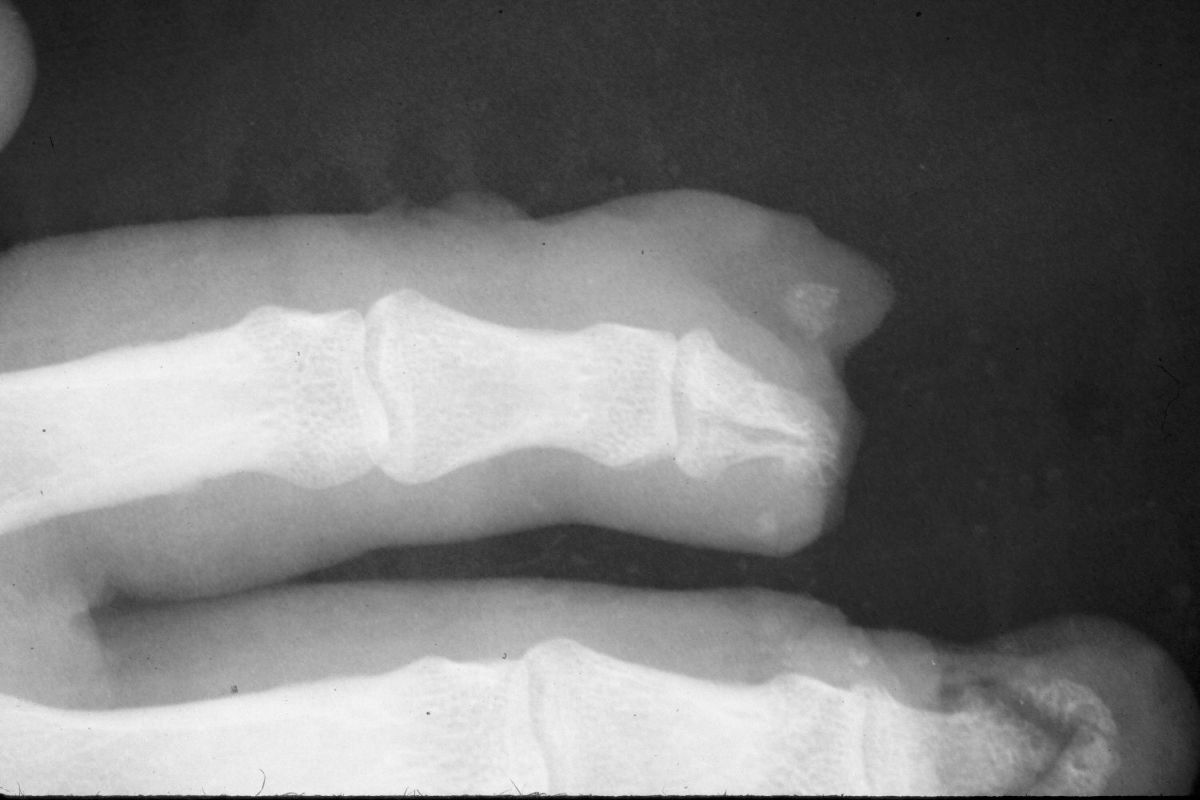

| The final result

was compromised by bone loss. The initial bone loss

was severe enough to warrant bone graft, but this

was contraindicated by the recent infection. |

| Over time, loss

of this structural support led to shortening and a

hook nail deformity. |

| Result at one

year. |

| Despite this, an

excellent resurfacing of the large defect has been